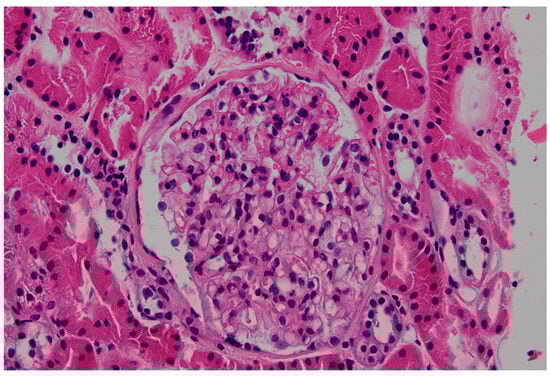

- Although endomyocardial biopsy (EMB, Figure 1) is not recommended to determine treatment efficacy or to follow up cardiac involvement, it can be considered as a confirmatory diagnostic tool in patients with a variant of uncertain significance (VUS) or suspected cardiac variant of FD [7]. In addition, for patients who are not able to discontinue anticoagulation, EMB could be a good alternative for kidney biopsy. Lamellar bodies and intracellular inclusions found in electron microscopy provide strong evidence to diagnose FD.